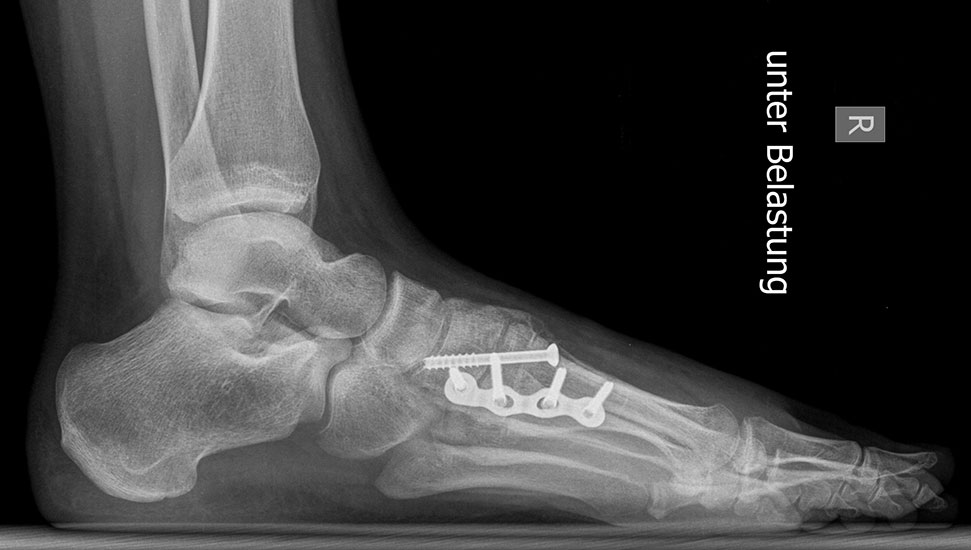

Röntgen

Standard ist die belastete Röntgenaufnahme des Fußes dorso-plantar und seitlich. Günstig ist eine Röhrenkippung von 10°-20°, um die Gelenke der Lisfranc-Linie einsehen zu können.

Bezüglich der Operationstechniken wird von früher häufig durchgeführten alleinigen Weich­teileingriffen am Großzehengrundgelenk aufgrund hoher Rezidivraten abgeraten 15. Die Operation nach Mc Bride mit lateralem Release, Exzision des lateralen Sesambeins, Abtragen der Pseudoexostose, Sehnenetransfer des M. adductor hallucis und mediale Kapselraffung zeigte unbefriedigende Mittel- und Langzeitergebnisse 16. Die Cerclage fibreux (mediale Kapselraffung) und das laterale Kapselrelease wird heute in Kombination mit einem knöchernen Eingriff angewendet. Bezüglich des Einsatzes von minimalinvasiven Operations­techniken vor Wachstumsabschluss liegen bisher keine Daten vor. Alle Osteotomien lassen sich nach Bedarf miteinander kombinieren. Es ist darauf zu achten, dass Osteotomien keine offenen Wachstumsfugen verletzen.

• medial aufklappende Cuneiforme I Osteotomie 1522

• Nach Schluss der Wachstumsfugen: TMT I Arthrodese nach Lapidus 2425